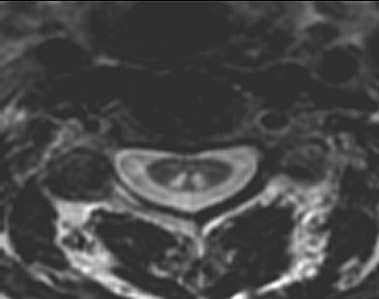

| This axial MRI scan shows changes of subacute combined degeneration of the spinal cord in a patient with pernicious anemia from vitamin B12 deficiency. Note the enhancement of the posterior columns in the region of the cervical cord above and the thoracic cord below. |